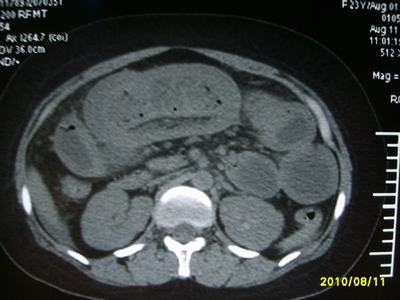

5天前突发腹痛剧烈难忍,伴解淡血水样便。近一天来腹痛缓解,没有明显的腹膜炎的体征。今天照的腹部ct。从ct上看感觉是一个绞窄性肠梗阻,但是现在没有腹痛。不好解释

高位肠梗阻(不全性),原因小肠(空肠)扭转,肠壁水肿增厚,成年人肠梗阻要排除合并占位,建议手术。

绞窄性肠梗阻_肠管套叠 扭转,肠壁明显水肿。

支持绞窄性肠梗阻,肠壁明显水肿并见有多发小泡状积气--肠坏死

考虑绞窄性肠梗阻并肠坏死。